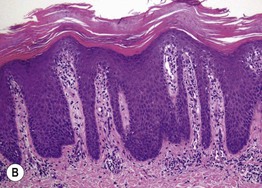

Fig. 1.8 Spongiotic dermatitis. A Acute allergic contact dermatitis to Toxicodendron radicans (poison ivy). The central black discoloration is due to the plant's resin. B Intercellular edema (spongiosis) and vesicle formation within the epidermis. Lymphocytes are also seen in both the epidermis and dermis. A, Courtesy, Kalman Watsky, MD; B, Courtesy, James Patterson, MD.